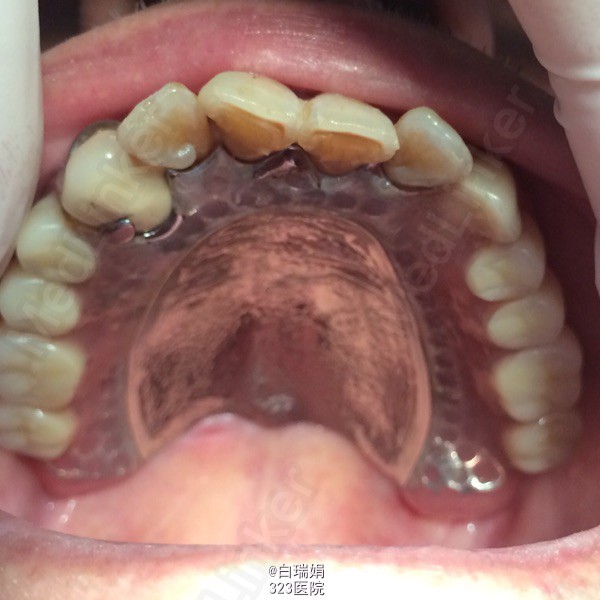

诊断:1、牙列缺损 2、左上烤瓷冠桥松动 3、左上3、4慢性根尖周炎 处理:1、拆除左上烤瓷冠桥,拔除左上5、7 2、左上3、4截冠后常规行根管治疗 3、左上3治疗后无症状制作根面磁性附着体 4、粘接根面附着体后取上下颌模型,纪录咬合关系,制作活动义齿 5、试戴蜡型,调整咬合关系,戴活动义齿,调合抛光,粘接另一半磁铁

戴牙五天后患者上腭后堤区出现溃疡,调改义齿,一周后患者复诊无不适。 希望各位同仁能提出宝贵的意见,共同学习